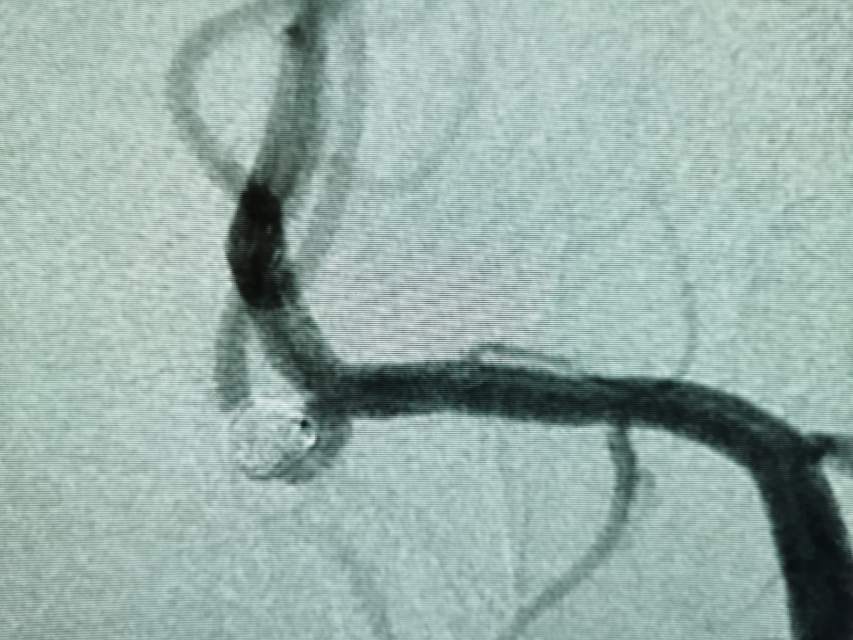

破裂的大脑中动脉动脉瘤二期支架植入

患者,中年男性,颅内动脉瘤破裂出血,急性期给予单纯弹簧圈大部致密栓塞(瘤颈少许残留),降低了急性期破裂出血的风险,急性期免除了使用抗血小板的顾虑和担心(如果使用支架),为了预防远期的复发,二期植入支架,就会安全多了